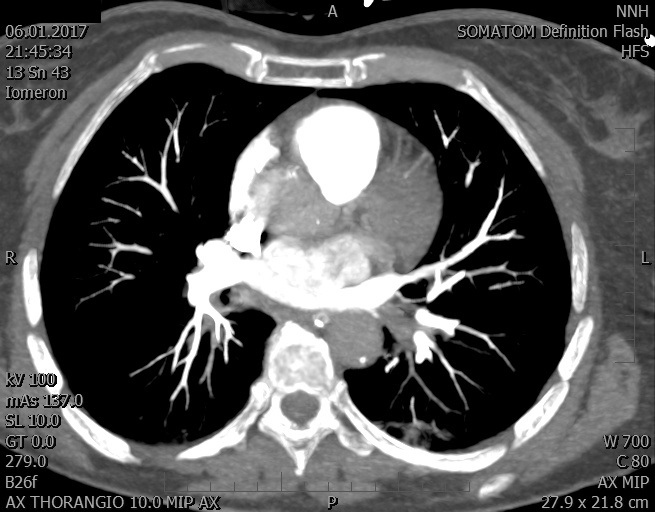

Video 1 - Akutní koronarografie prokázala normální nález na věnčitých tepnách s výjimkou suspekce na lehký spasmus na pravé koronární tepně.Echokardiograficky byla zjištěna těžká dysfunkce dilatované levé komory s nezvětšenou pravou komorou (video 2).

Video 2 - Echokardiograficky byla zjištěna těžká dysfunkce dilatační levé komory s nezvětšenou pravou komorou.Pro nejasnou příčinu zástavy jsme provedli i vyšetření výpočetní tomografií (CT), které vyloučilo plicní embolizaci (série 1 - soubory na konci článku). V den přijetí při přetrvávající oběhové nestabilitě byla nemocná opakovaně defibrilována pro fibrilaci komor se stabilizací rytmu po podání amiodaronu a mesocainu. Dle hemodynamických měření se jednalo o těžký kombinovaný šok. Vstupní laboratorní vyšetření bylo bez větších pozoruhodností. Posléze jsme doplnili anamnézu od příbuzných a zjistili, že pacientka užila do dvou hodin před srdeční zástavou první tabletu amoxicilinu na lehký respirační infekt. Při nevýtěžnosti vstupních vyšetření a nových anamnestických informacích jsme doplnili 14 hodin po kolapsu vyšetření koncentrace tryptázy v séru, která byla extrémně zvýšena (tabulka 2), což nás vedlo k podezření na anafylaxi.